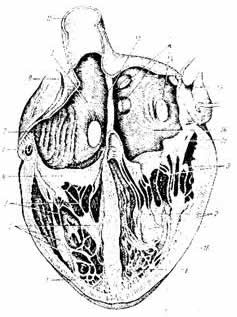

Строение стенки сердца

Стенка сердца состоит из трех слоев: внутреннего - эндокарда, среднего - миокарда и наружного - эпикарда.

Эндокард выстилает изнутри поверхность камер сердца, он образован особым видом эпителиальной ткани - эндотелием. Эндотелий имеет очень гладкую, блестящую поверхность, что обеспечивает уменьшение трения при движении крови в сердце.

Миокард составляет основную массу стенки сердца.

Он образован поперечно - полосатой сердечной мышечной тканью, волокна которой в свою очередь располагаются в несколько слоев. Миокард предсердий значительно тоньше, чем миокард желудочков. Миокард левого желудочка в три раза толще, чем миокард правого желудочка. Степень развитости миокарда зависит от величины работы, которую выполняют камеры сердца. Миокард предсердий и желудочков разделен слоем соединительной ткани (фиброзное кольцо), что дает возможность поочередного сокращения предсердий и желудочков.

Эпикард - это особая серозная оболочка сердца, образованная соединительной и эпителиальной тканью.

| Рис. 34. Внутреннее строение сердца.